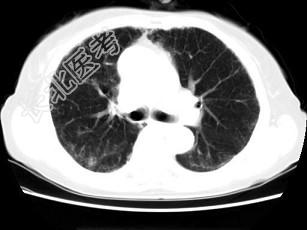

- 单项选择题女,35岁, 咳嗽,咳痰, 发热3月余,胸部CT如图, 最可能的诊断为 ( )

A、类风湿肺炎

B、红斑狼疮性肺炎

C、间质性肺炎

D、肺结节病

E、肺部感染